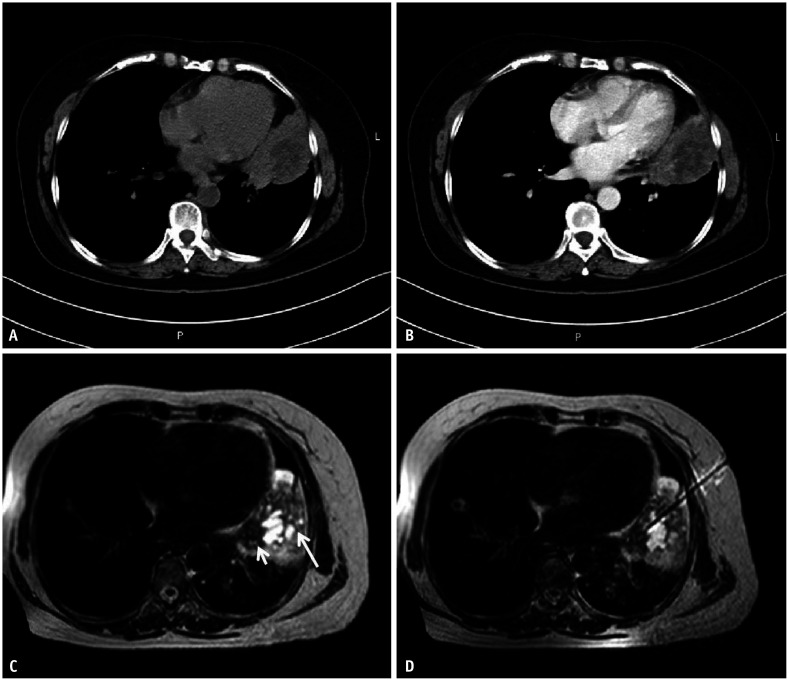

Materials and methods: In this single-center study, MRI-guided percutaneous coaxial cutting biopsy was performed for 107 suspicious central lung lesions with associated post-obstructive atelectasis in 107 patients between July 2015 and December 2020. A fast T2-weighted imaging (T2WI)-turbo spin echo (TSE) sequence and an enhanced fast T1-weighted imaging (T1WI)-TSE sequence were used to identify, localize, and biopsy lung lesions, and diffusion-weighted imaging (DWI) was used as a supplementary sequence for identifying the lesion location. The final diagnosis was confirmed by surgical histopathology or clinical follow-up for a minimum of 24 months. The sensitivity, specificity, and accuracy for diagnosing lung malignancies were calculated, and the complications were recorded for each case.

Results: Using multiparameter MRI, central lung lesions could be clearly distinguished from post-obstructive atelectasis in 96 patients (89.7%). The sensitivity, specificity, and accuracy of MRI-guided percutaneous biopsy for diagnosing lung malignancy was 97.0% (98/101), 100% (6/6), and 97.2% (104/107), respectively. Self-limited hemoptysis occurred in three patients. Pneumothorax occurred in five patients, of which none required pleural drainage. No serious procedure-related complications were observed.